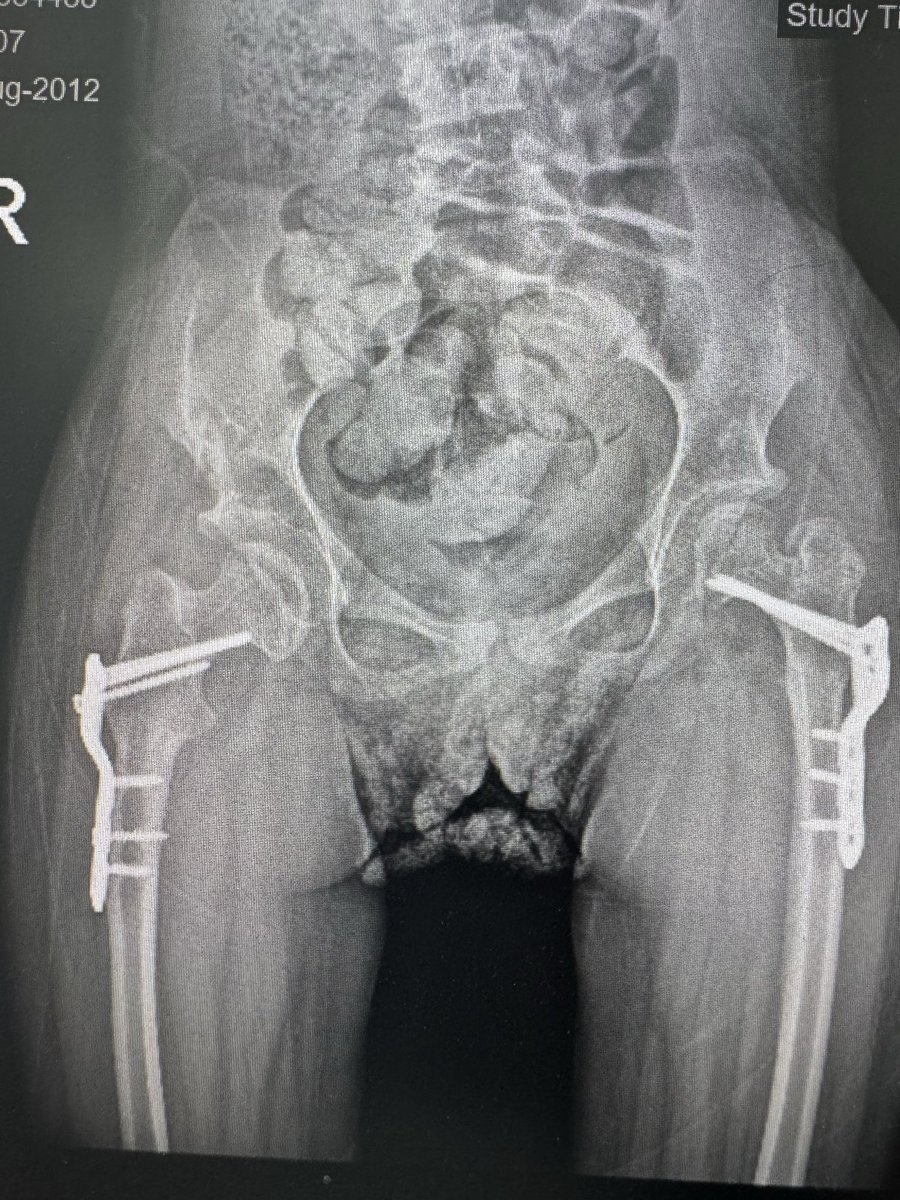

@NabilAlassaf ما شاء الله يادكتور الحوض بعد العملية رجع زى الطبيعى بالظبط...بس السؤال الخلافى هل ينفع نعمل عملية الخلع فى الرجلين وهل الطفل بيقدر يتحمل ؟ وموضوع ازالة الشرايح له وقت ولا عادى يقدر يعيش بيه؟....وجزاك الله كل خير..